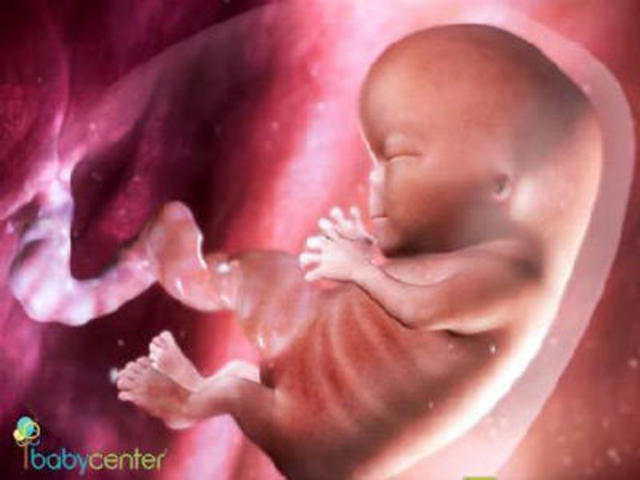

week 11

Some things the baby is doing during week 11 are growing hair follicles, fingernails, and ovaries. She now has hands and feet in front of her body, with ears nearly in their final shape, open nasal passages on the tip of her tiny nose, a tongue in the mouth, and visible nipples.

http://www.whattoexpect.com/pregnancy/week-by-week/week-11.aspx